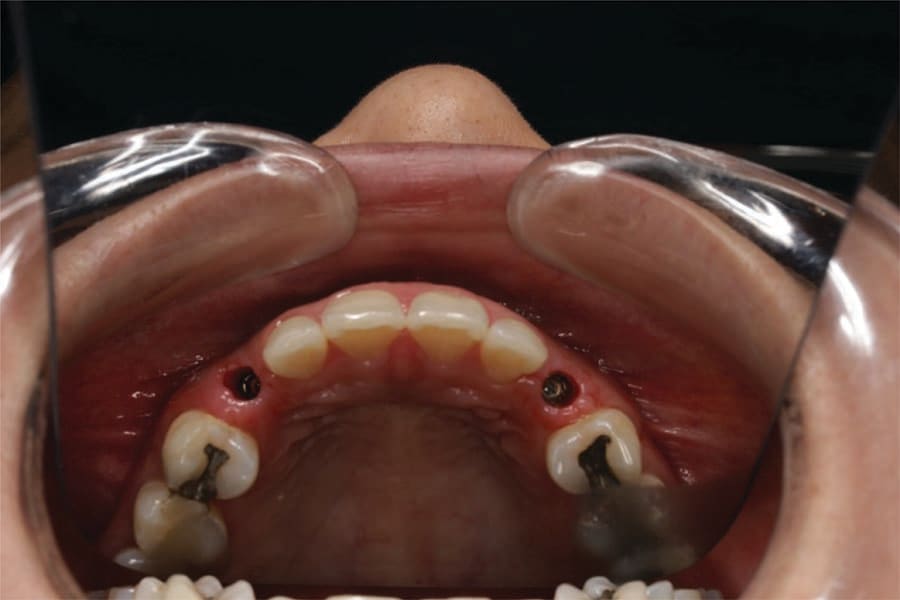

At 3 months post implant placement the patient returned to initiate restoration of the implants. A CBCT was taken to check bone levels on the integrated implants. Panoramic and occlusal views were analyzed verifying the implants in contact with the surrounding bone and appeared ready to restore (Figure 13 and Figure 14). Local anesthetic was administered, and the implants were uncovered with the Solea CO2 laser and the healing screws exposed (Figure 15). Healing abutments were placed in the implants and the patient scheduled for impressions.